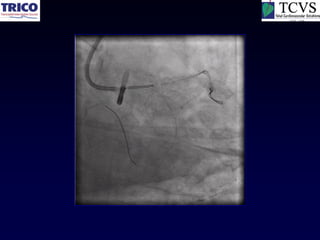

LMCA Bifurcation Rota-Stent

LMCA intervention…

A real nightmare